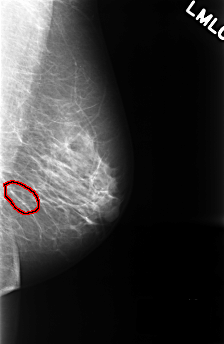

C_0325_1.LEFT_MLO

LEFT_MLO LINES 4472 PIXELS_PER_LINE 2912 BITS_PER_PIXEL 12 RESOLUTION 50 OVERLAY

FILE: C_0325_1.LEFT_MLO.OVERLAY

TOTAL_ABNORMALITIES 1

ABNORMALITY 1

LESION_TYPE CALCIFICATION TYPE PUNCTATE DISTRIBUTION CLUSTERED

ASSESSMENT 4

SUBTLETY 4

PATHOLOGY BENIGN

TOTAL_OUTLINES 1

BOUNDARY